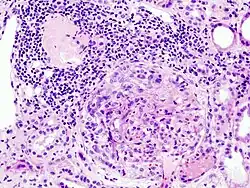

Histopathological image of crescentic glomerulonephritis in a patient with MPO-ANCA positive rapid progressive glomerulonephritis. Hematoxylin & eosin stain.

Rapidly progressive glomerulonephritis (RPGN) is a syndrome of the kidney that is characterized by a rapid loss of kidney function,[4][5] (usually a 50% decline in the glomerular filtration rate (GFR) within 3 months)[5] with glomerular crescent formation seen in at least 50%[5] or 75%[4] of glomeruli seen on kidney biopsies. If left untreated, it rapidly progresses into acute kidney failure[6] and death within months. In 50% of cases, RPGN is associated with an underlying disease such as Goodpasture syndrome, systemic lupus erythematosus or granulomatosis with polyangiitis; the remaining cases are idiopathic. Regardless of the underlying cause, RPGN involves severe injury to the kidneys' glomeruli, with many of the glomeruli containing characteristic glomerular crescents (crescent-shaped scars).[7]